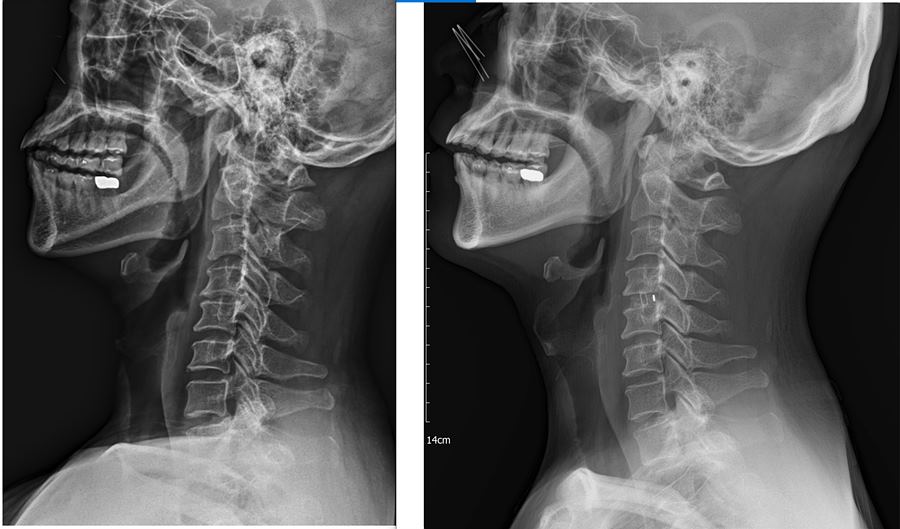

3. X-Ray 세로 사진 : 오른쪽이 수술 후

. 신경공을 더 넓히지는 못했지만 케이지를 넣음으로써 분절간 높이가 수술 전보다 확연히 높아졌다.

. 교수님도 분절 사이가 높아졌으니 그만큼 공간이 더 생겼고 크게 걱정하지 않아도 된다고 하셨다.